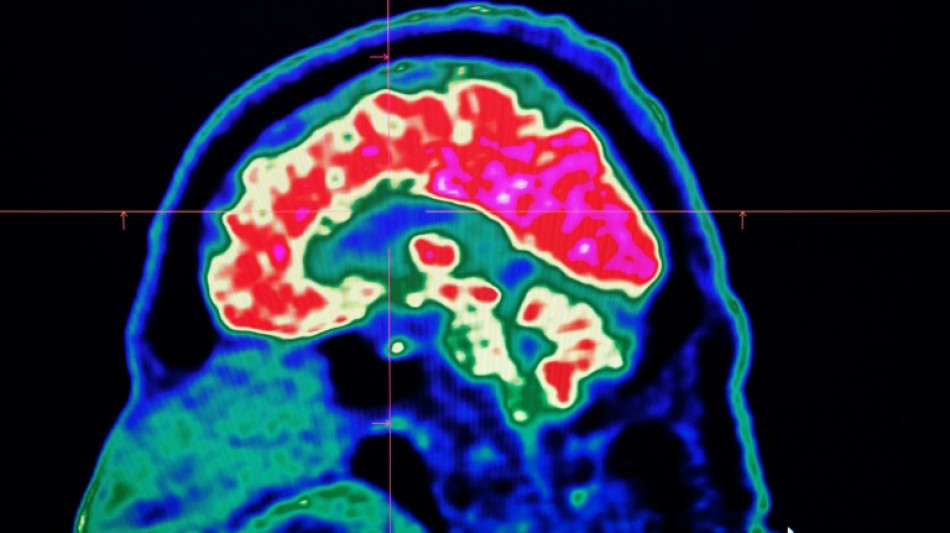

Surging nervous system disorders now top cause of illness: study / Photo: © AFP/File

Conditions affecting the nervous system -- such as strokes, migraines and dementia -- have surged past heart disease to become the leading cause of ill health worldwide, a major new analysis said on Friday.

More than 3.4 billion people -- 43 percent of the global population -- experienced a neurological condition in 2021, far more than had previously been thought, the analysis found.